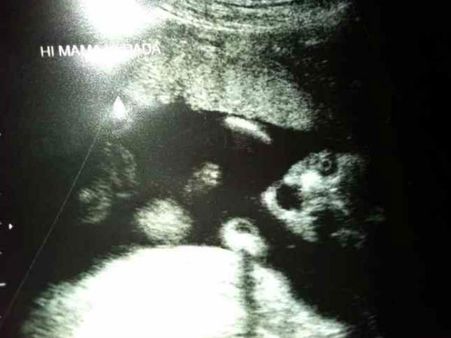

Picture# 2 Is It Looking Here?

Is the baby a poser even before being born? Well, looks like he/she is surely one, as you can see the foetus pose like a pro! Those haunting eyes will surely not let many sleep in peace!